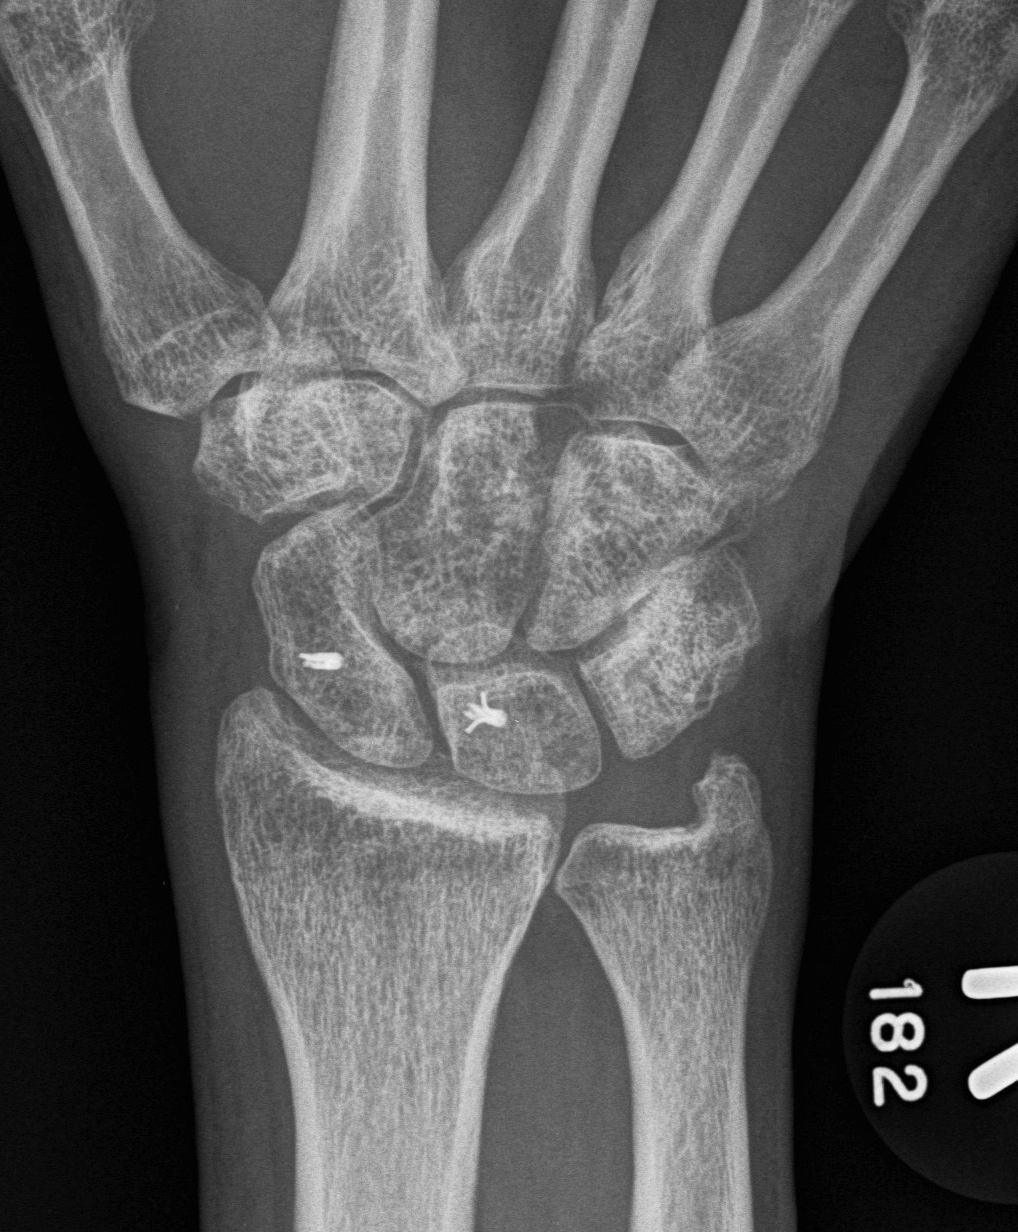

AP

Terry Thomas sign

- increased scapholunate interval

- > 3 mm compared with other side

Cortical Ring sign

- end-on view of cortex of distal pole of scaphoid

Scaphoid shortened

- due to palmar flexion